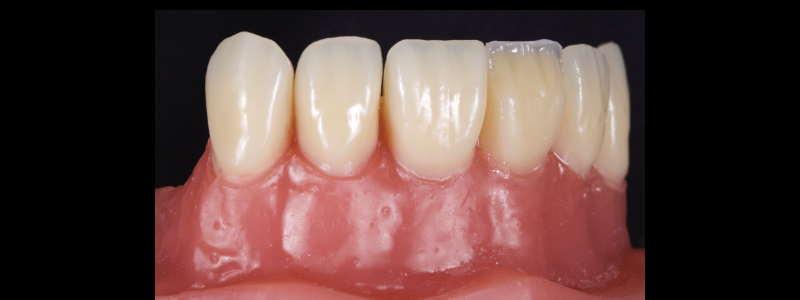

They are placed to overlap the dentin resin masses, finishing at the inferior aspect of the infinity bevel. Since the chromatic enamels have a degree of translucency, the thin layer at the margin hides the restoration margin.

Towards the incisal, dentin mamelons are formed with a posterior occlusal carver (Fig. 16) and then “feathered” with an explorer (Fig. 17). This gives a highly natural appearance.

The chromatic enamels are built to full contour in the gingival and mid thirds but are under contoured in the incisal third (Figs. 18 and 19).